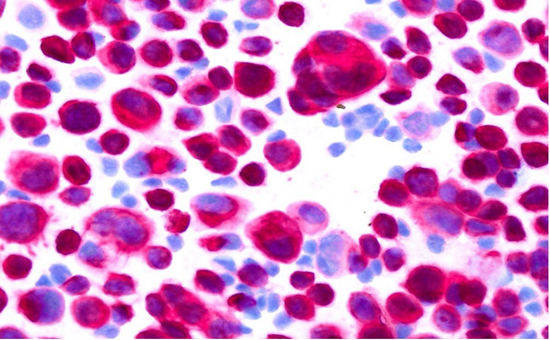

Due to progressive pleomorphic keratic precipitates, anterior chamber cells, vitreous cell infiltration and now agglomeration of hyperreflective, pre-retinal deposits as detected by OCT (Figure 2), a second diagnostic vitrectomy with repeated pathological examination and Borrelia PCR was performed. Cytopathological examination of cytospin preparations revealed cell-rich material with anisometric and polymorphic cells. These corresponded mostly to atypical large epithelial cells with positive immunocytological staining for cytokeratin AE1/AE3 antibody, and a small population of interspersed small T lymphocytes positive for CD3. Accordingly, these findings were interpreted as carcinoma cells in the vitreous, consistent with metastatic spread of the known SCC of the bladder. (Figures 3, 4) Further evaluation by a second reference pathology laboratory confirmed the presence of numerous atypical epithelial cells consistent with a non–small cell carcinoma. No evidence of malignant lymphoma was found.

Figure 3: Atypical large epithelial cells with positive immuncytological staining for cytokeratin AE1/AE3 antibody.

Figure 4: Atypical large epithelial cells, Pappenheim stain.